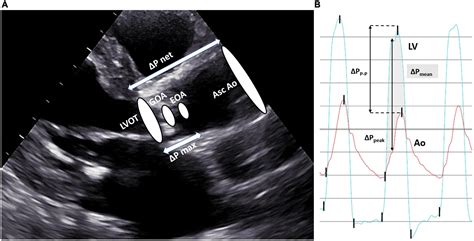

At its core, Severe Aortic Stenosis occurs when the aortic valve leaflets stiffen, thicken, or fuse together, often due to calcium deposits. In a healthy heart, the valve opens fully during contraction to allow blood to exit the heart. In a stenotic state, the opening is severely restricted, creating a pressure gradient between the left ventricle and the aorta. Over time, this chronic overexertion leads to left ventricular hypertrophy, where the heart muscle thickens to compensate for the resistance, eventually risking heart failure if left unaddressed.

Physicians typically diagnose Severe Aortic Stenosis through a combination of physical examinations and advanced imaging technologies. The most common diagnostic tool is the echocardiogram, which provides a real-time visualization of the valve’s movement and measures the severity of the obstruction.

• severe aortic stenosis gradient